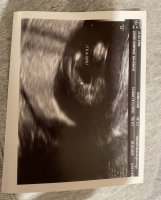

That's good. I know it feels far but it will be here soon. I hope everything goes smoothly until then.@Nima I was able to get my scan moved up to the 13th from the 20th, thankfully, but that still seems like a lifetime away.